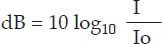

Intensity is measured in relative intensity relative intensity

where dB is decibel

I Intensity at a point of interest

Io is original intensity or reference intensity